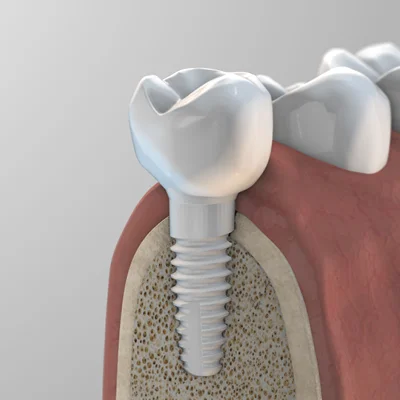

รากฟันเทียมเซรามิก (Ceramic Dental Implants) เป็นเทคโนโลยีการปลูกรากฟันเทียมที่ใช้สำหรับทดแทนรากฟันที่ถูกถอนออกไป โดยวัสดุหลักที่ใช้ผลิตคือ เซอร์โคเนีย (Zirconia) ซึ่งเป็นเซรามิกชนิดหนึ่งที่มีคุณสมบัติโดดเด่นในด้านความแข็งแรงทนทานสูง เทียบเท่ากับโลหะ แต่มีสีขาวเหมือนฟันธรรมชาติ ทำให้เป็นทางเลือกที่ได้รับความสนใจอย่างมากในวงการทันตกรรมความงามและการแพทย์องค์รวม (Holistic Dentistry) เนื่องจากเป็นวัสดุที่ไร้โลหะ 100% (Metal-free)

ในอดีต รากเทียมที่ใช้กันอย่างแพร่หลายคือรากเทียมที่ทำจากไทเทเนียม ซึ่งมีความแข็งแรงและใช้งานได้ดีเยี่ยมมาโดยตลอด แต่ในบางกรณีก็อาจมีข้อกังวลเรื่องสีเทาของโลหะที่อาจจะโผล่ให้เห็นบริเวณขอบเหงือก หรือในผู้ป่วยบางรายที่กังวลเรื่องการแพ้โลหะ

- วัสดุ: รากเทียมเซรามิกทำจาก เซอร์โคเนีย ซึ่งเป็นเซรามิกชนิดหนึ่ง มีสีขาวทั้งหมด ไม่มีส่วนประกอบของโลหะ ส่วนรากเทียมทั่วไปทำจาก ไทเทเนียม ซึ่งเป็นโลหะที่มีสีเงิน

- ความสวยงาม: เนื่องจากมีสีขาวเหมือนฟันธรรมชาติ รากเทียมเซรามิก จึงไม่เกิดเงาดำหรือสีเทาบริเวณขอบเหงือกเหมือนกับรากเทียมไทเทเนียม ทำให้เหมาะอย่างยิ่งสำหรับการปลูกรากฟันหน้า

- เมื่อรากเทียมยึดติดกับกระดูกอย่างแน่นหนาแล้ว ทันตแพทย์จะทำการใส่เดือยฟัน (Abutment) และครอบฟัน (Crown) ที่ทำจากวัสดุที่มีสีเหมือนฟันจริง เพื่อให้ได้ผลลัพธ์ที่สวยงามและใช้งานได้ตามปกติ